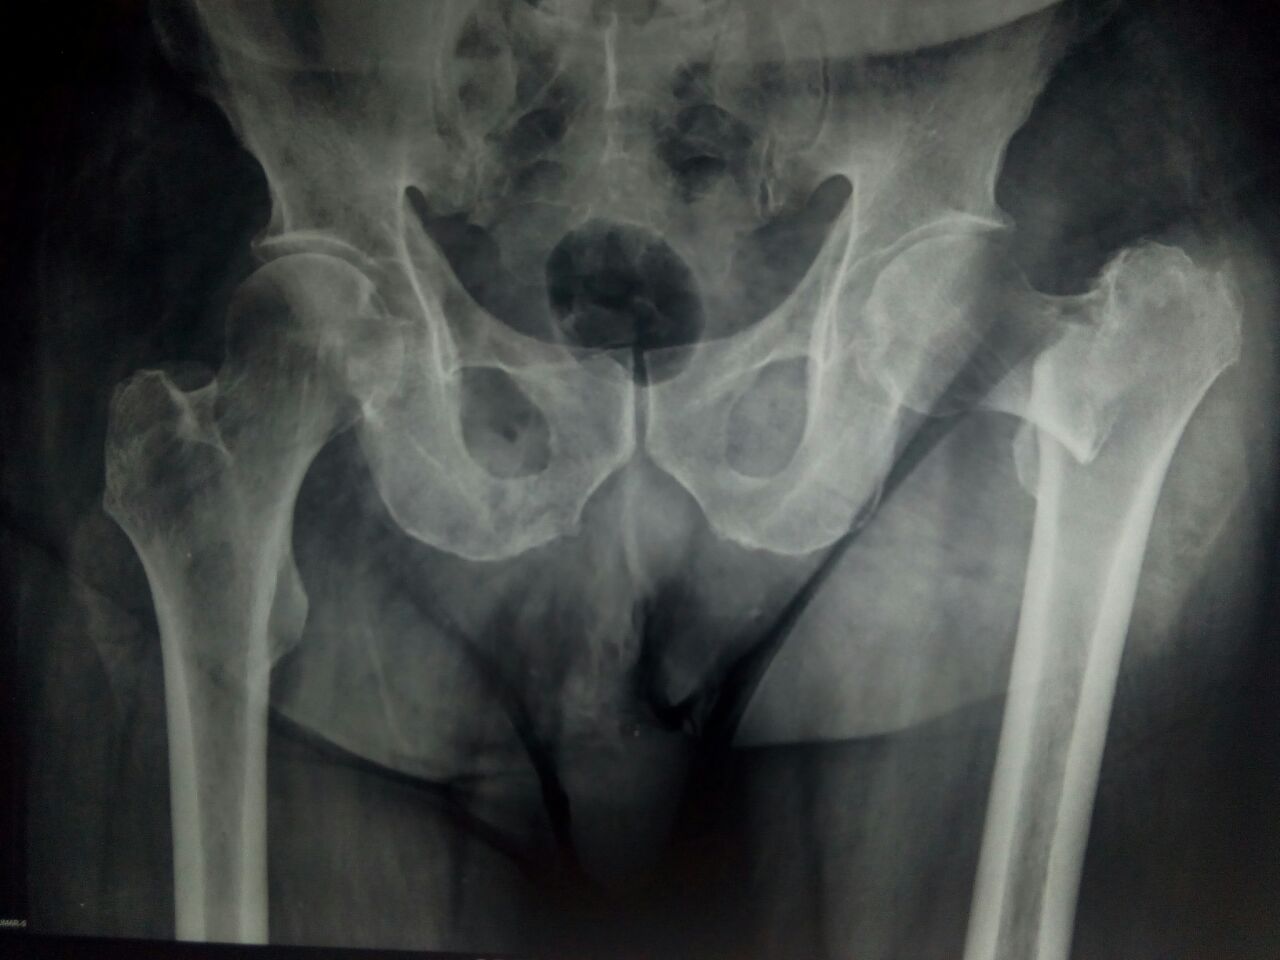

Pre-Operation

Successful Comminuted Intertrochanteric Fracture - Surgery for an Old-Man

The Patient was 80 Years Old Man had fallen down unfortunately and got Comminuted Intertrochanteric Fracture .They approached Sooriya Hospital on 15th of July 2018 for the Treatment. The patient with so much of complications now been treated by Imported Bipolar Hemi Arthroplasty by the Doctor P.Sankaralingam (M.S (Ortho), DNB (Ortho), MNAMS) on 16.07.2018. The successful surgery made by our doctor, makes the patient to walk immediately the next day with full weight bearing walker.